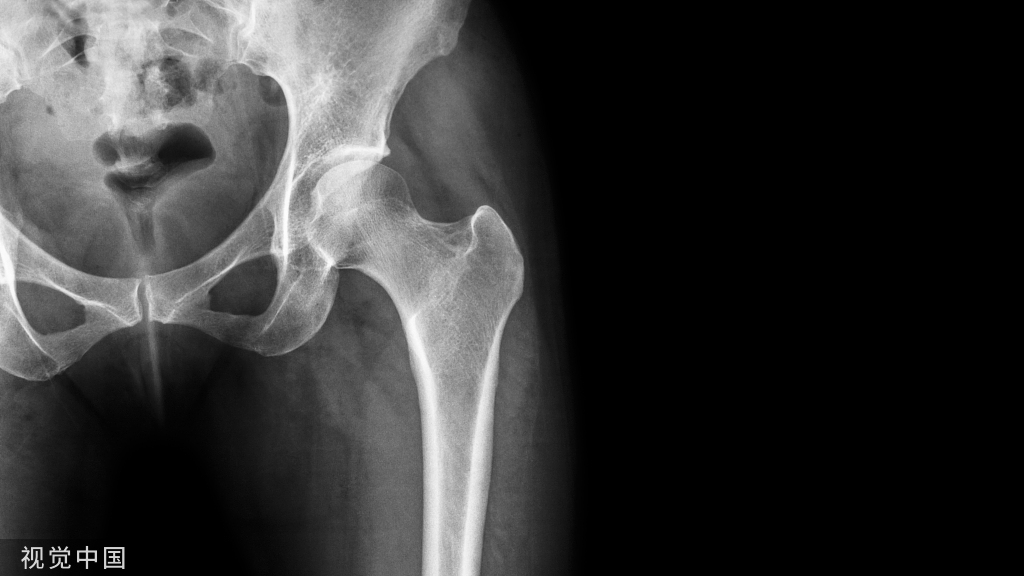

正常腰椎间盘表现

正常腰椎间盘后缘不超过椎体骨性终板的后缘,且中部略有凹陷呈肾形。

一个健康的45岁男性的L4椎间盘的轴状面观。

髓核区及周围的纤椎环区。

靠近L5神经根的椎间盘后缘的凹度,这是正常健康椎间盘的象征。

L4发出神经根更靠侧方一点。这就不难理解为什么如果有大的椎间盘突出或椎管狭窄,发出神经根L4及过往神经根L5将同时受压。

在此图中,可清楚地看到悬挂在硬膜囊内的细小的神经根(L5神经根及S1神经根),它们以不完全有绪地状态排列着。注意,神经孔是很开阔的(浅黄色区),表明没有因邻近椎间关节问题形成在的椎管狭窄。T2加权象对于察看退化性椎间盘病是最好的,因为T2像将富含水份的结构表现为亮白色, 含水少的区域表现为黑色。

位于椎体之间的椎间盘应是白色的(含水多)。注意黑颜色(脱水的)的L5椎间盘(L5与骶骨之间的椎间盘),这代表了中度到重度的退化性椎间盘病。